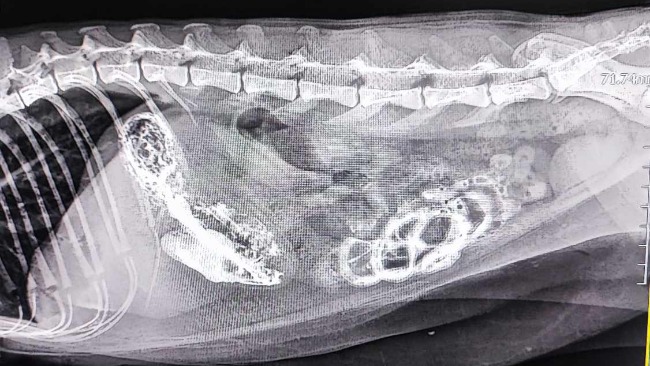

Tydzień temu Alfik przestał jeść. Rozpoczęliśmy całą diagnostykę: USG jamy brzusznej, badania z krwi, RTG, w tym RTG z kontrastem.

Okazało się, że przewód pokarmowy kocurka jest zapchany jego własnymi kłakami.

W lecznicy podjęto próbę leczenia zachowawczego- jeździliśmy codziennie na kroplówki i leki przyspieszające pasaż przewodu pokarmowego. Niestety nie dawało to pożądanego efektu, a u Alfika rozwinęła się żółtaczka mechaniczna- bilirubina we krwi przekroczyła pięciokrotnie górną granicę normy, a próby wątrobowe były bardzo wysokie, Alfik zżółkł jak cytrynka. Trzy dni temu Alfik został operowany, a z jego żołądka i jelit zostały wyjęte tzw. bezoary, czyli ciała obce utworzone ze zbitego z sobą futra.